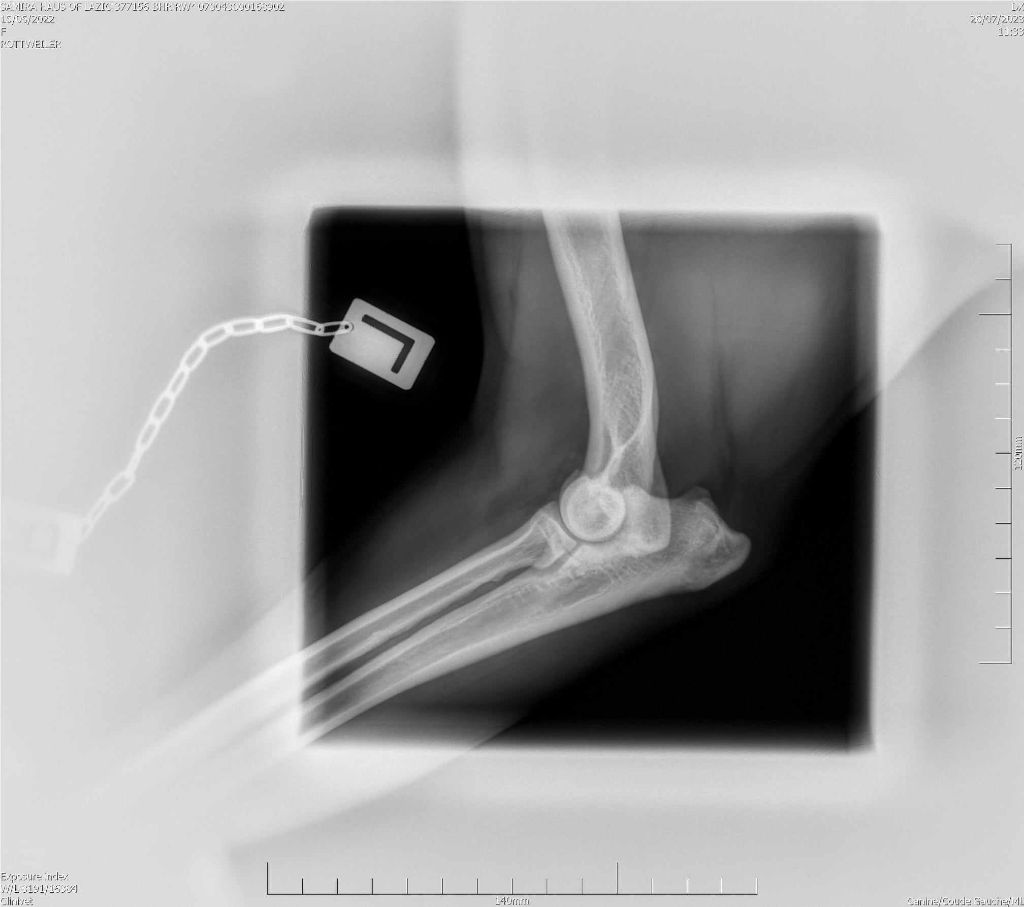

RADIO COUDE OFFICIELLE

COUDE SUITE

ADN : FAIT DYSPLASIE COUDES : ED0 DYSPLASIE HANCHES : HDA JLPP : CLEAR |